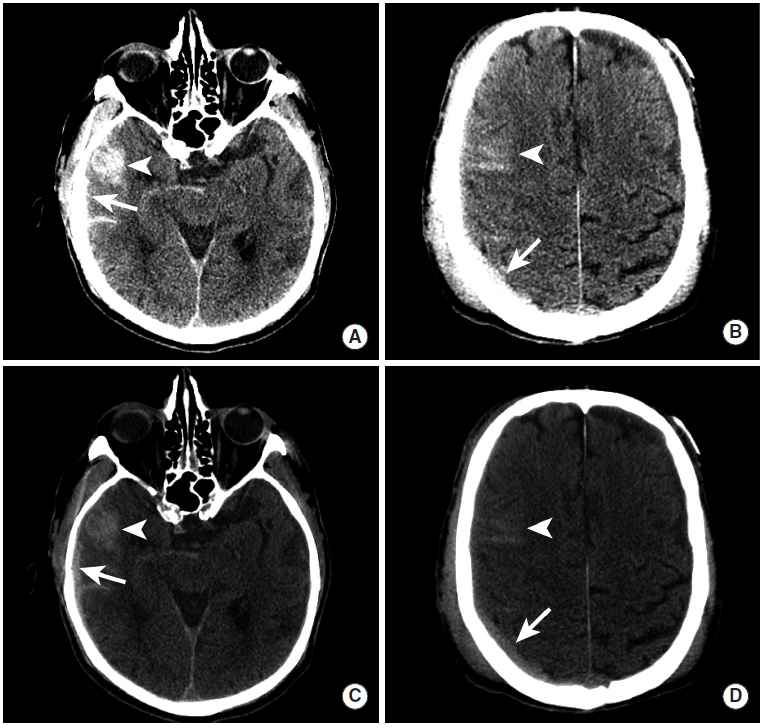

硬膜下血肿

图3

为了清楚地看到病变,CT的窗宽窗位做了一些调整。与硬膜下窗(图C、D)相比,病变在标准脑窗(图A、B)上不太明显。图中可见右前颞叶出血性挫伤和覆盖脑沟的蛛网膜下腔出血(三角箭头),骨板下可见弧形硬膜下血肿灶(长尾箭头)。

图4

本例患者由于巨大的硬膜下血肿引起了脑疝。平扫CT显示左侧巨大硬膜下血肿(长尾箭头),基底池受压消失(图A,三角箭头),大脑镰下疝形成(图B、C,三角箭头)和左侧小脑幕切迹疝(图C,虚线箭头)。